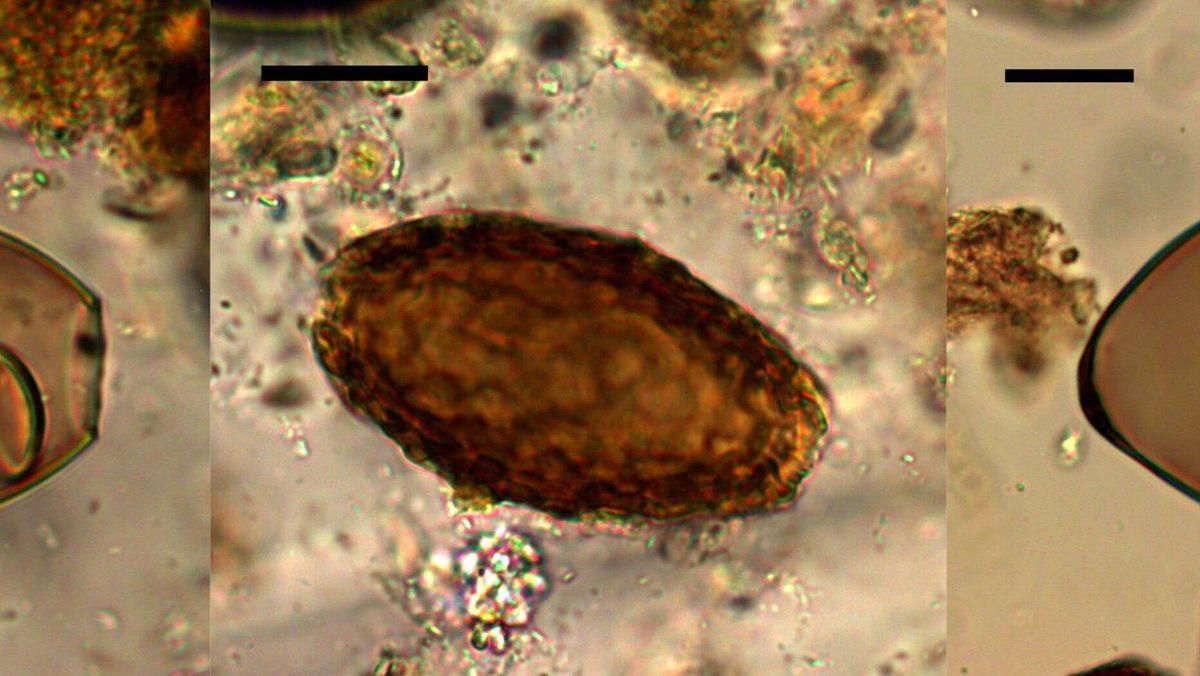

Fosilleşmiş olan dışkılar içerisinde son derece güzel bir şekilde muhafaza edilmiş parazit yumurtalarıyla karşılaşıldı. Araştırmacılar, bu parazitlerin insan vücudunda barınabilmesi için balık ve deniz ürünlerinin çiğ bir şekilde tüketilmiş olması gerektiğini söyledi.

Araştırmanın başyazarı Mitchell, dev böbrek solucanlarının büyüdükleri böbreği yok edebileceğini ve bizim de yalnızca iki adet böbreğimiz olduğunu belirtti. Bu nedenle bir insanın böbreğinde solucan çıkması sonucunda kişinin böbrek yetmezliğinden ölebileceği belirtildi. Araştırmanın sonuçları pek iç açıcı olmasa bile Mitchell ve ekibi araştırmadan memnun olduklarını ve bulgularının bilimsel araştırmalar için büyük önem arz ettiğini belirtti.